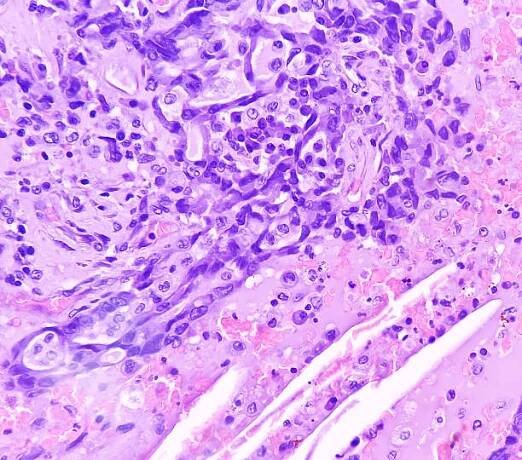

adenokarcinom plic. maligní buňka. nátěry ukazují buněčný materiál atypických epiteliálních buněk, buňka vykazuje pleomorfii s prominentními jádry a cytoplazmou. rakovina plic. - histiocyt - stock snímky, obrázky a fotky